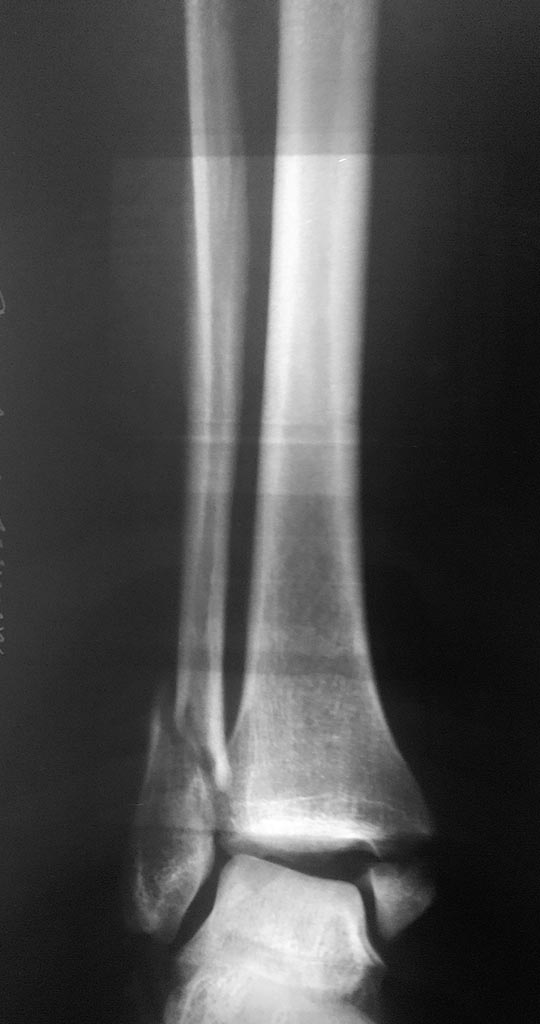

Здравствуйте. Женщина 56 лет, чрезсиндесмозный 3х-недельный перелом лодыжек.

Мнения коллег о сохраняющимся подвывихе стопы разошлись. Смущает визуальное расширение медиального лодыжечного пространства, хотя вся суставная щель примерно одинакова и равна 4-5 мм.

Для оценки желательно сделать сравнительные снимки обоих голеностопных суставов в проекции мортис, без них сложно дать ответ. Не совсем понятно полностью ли восстановлена длина латеральной лодыжки.

Подвывиха нет..Не хватает компрессионного межфрагментарного винта на наружной лодыжке, но не корично.Сделайте снимок здоровой ноги и наложите